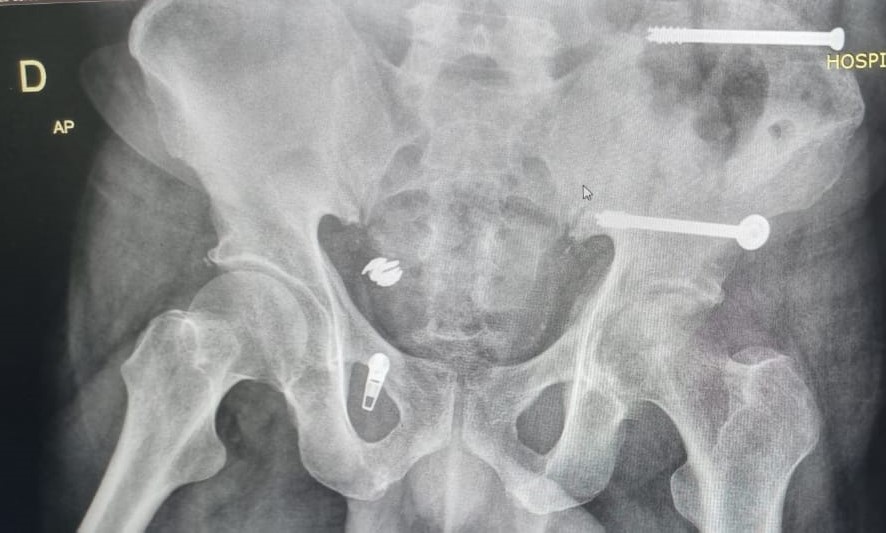

• Fraturas do Anel Pélvico;

• Próteses de Quadril (Primárias  e Revisões);

• Cirurgia do Quadril;